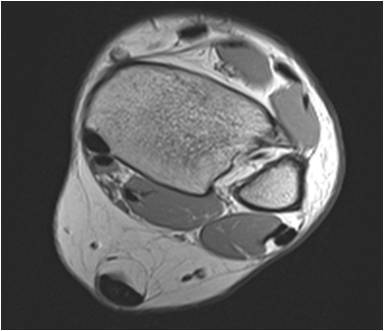

Physician Assistant Lower Limb and Thorax Written Examination - Radiology Pool

Gallery of Unlabled Radiographs from Lecture (Dr. French) - 2020

Click a thumbnail to enter the gallery display. Click the file name link at the bottom left of the gallery display to view the image at high resolution.